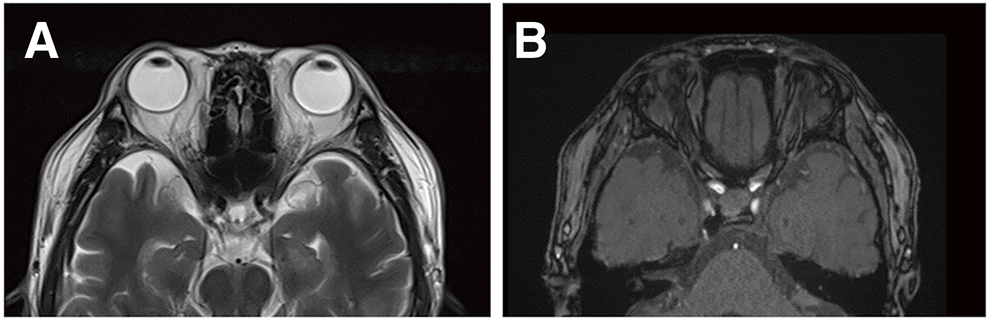

A man in his 50s with well-controlled diabetes presented with right eye congestion that had developed 1 week earlier. Ophthalmological examination revealed a visual acuity of 1.2 in the right eye (1.0 in the left) with no impairment of extraocular movement. The intraocular pressure (IOP) in the right eye was 27 mmHg (left 17 mmHg), and conjunctival congestion was noted in the right eye. MRI of the head showed 22 mm of right eye proptosis, dilatation of the intraorbital veins, and detection of the right CS (Fig. 2A and 2B). Diagnostic cerebral angiography revealed a right CS dural AVF fed by both internal carotid arteries, the right accessory meningeal artery, and the CS branch of the middle meningeal artery. The shunted pouch was located in the medial-lateral portion of the right CS, with drainage into the superior ophthalmic vein (SOV) (Fig. 2C–2F). Neither IPS was contrasted. Endovascular TVE via both IPSs was planned.

Fig. 2 Pre-procedural imaging. (A) T2-weighted MR imaging shows right eye proptosis and dilatation of the intraorbital vein (arrow). (B) A source image from MR angiography shows the detection of the right CS (arrow). (C) The arterial phase of right CCAG reveals early detection of the right CS (arrows). Right SOV is refluxed in lateral view (asterisk). (D) The venous phase of right CCAG shows reflux into the dilated right SOV (asterisks). Right IPS is not detected. (E) The arterial phase of left CCAG shows early detection of the right CS (arrows). (F) The venous phase of left CCAG at the cervical level shows no contrast of bilateral IPSs. In the angiographic imaging (CF), the right and left sides correspond to anteroposterior and lateral views, respectively. CCAG: common carotid angiography; CS: cavernous sinus; IPS: inferior petrosal sinus; SOV: superior ophthalmic vein

Post-operatively, the patient’s proptosis and conjunctival congestion completely resolved within 1 week. At 6 months post-procedure, the IOP had normalized, and no recurrence was observed. MRI at 6 months post-procedure showed no signs of proptosis (Fig. 4).

Fig. 4 Imaging 6 months after the procedure. (A) T2-weighted MR imaging shows complete recover of the proptosis and dilatation of the intraorbital vein. (B) A source image from MR angiography shows no visualization of the right cavernous sinus.